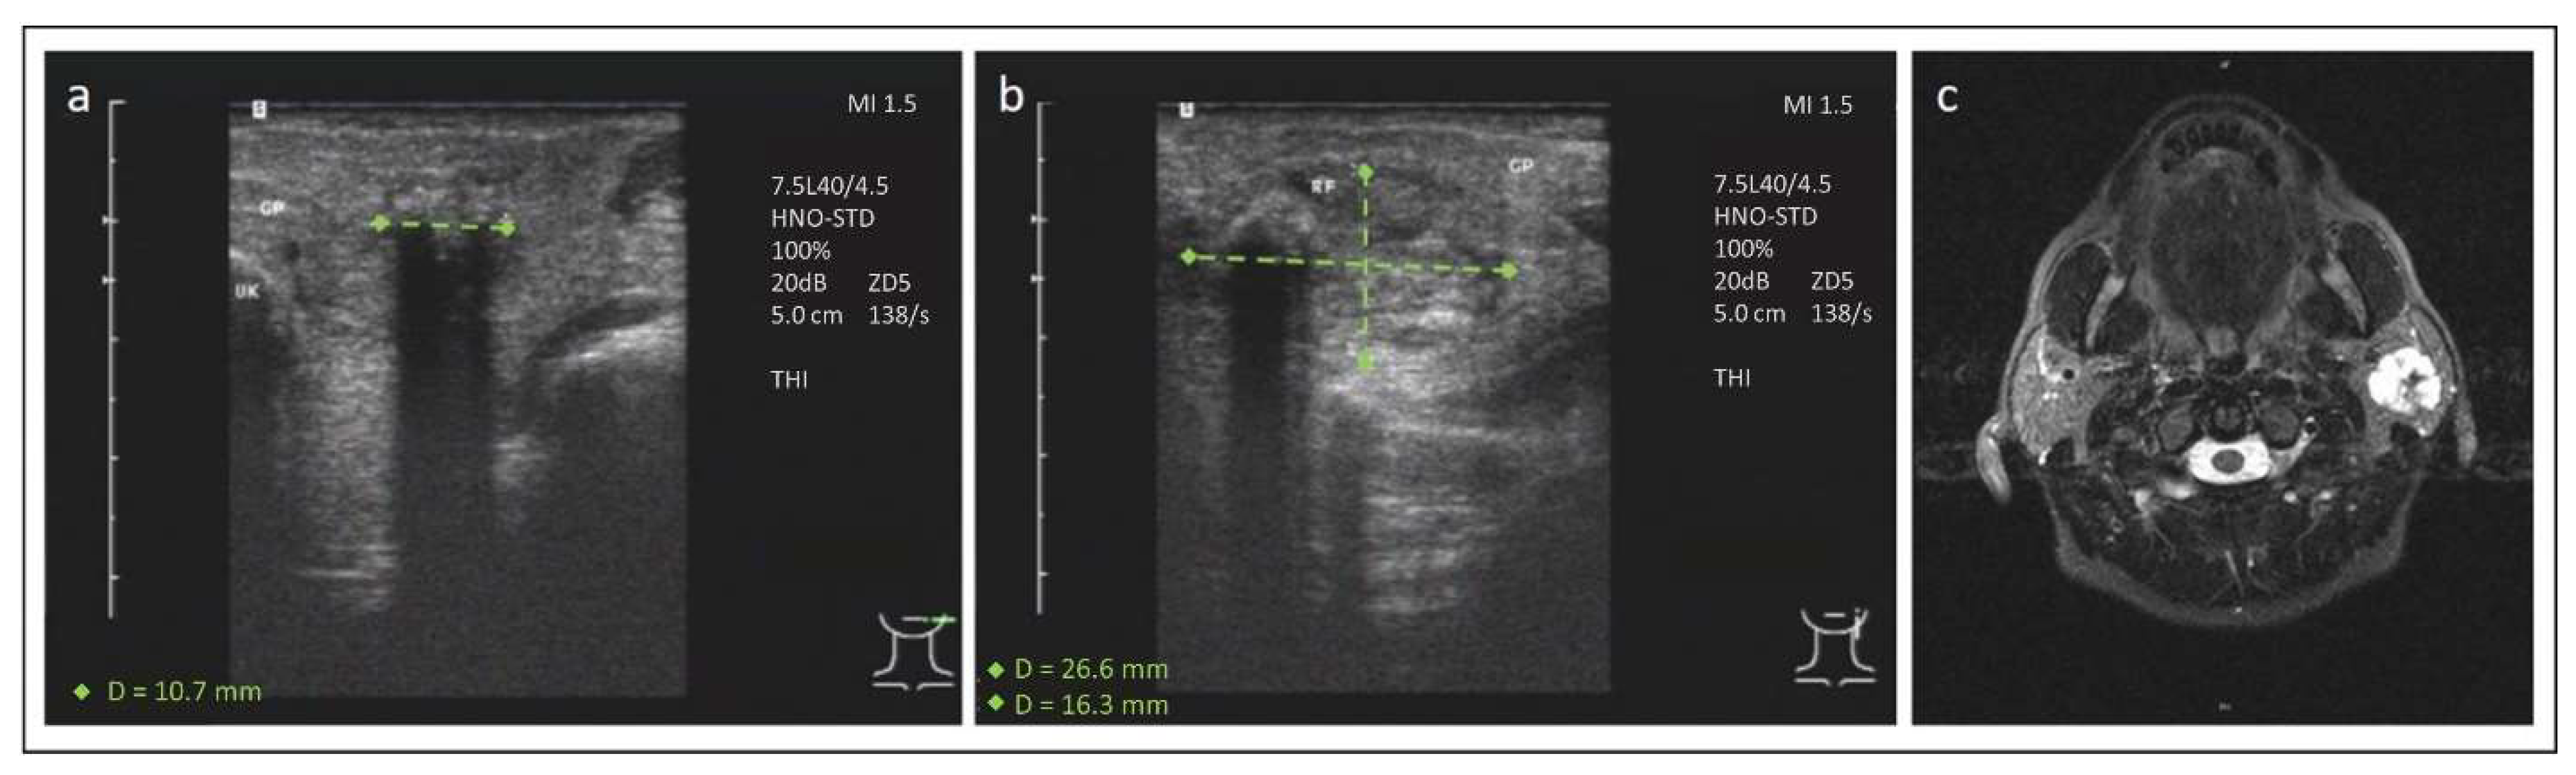

3. Case 2